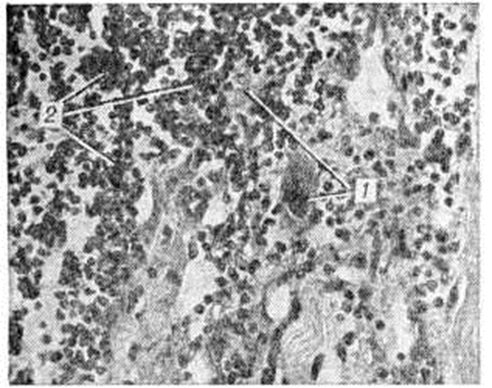

Отдельные клинические формы миозита. Гнойный миозит вызывается чаще всего стафилококком, а также стрептококком, пневмококком, анаэробной инфекцией и другими возбудителями. Развивается обычно остро на фоне очагового гнойного процесса или в связи с септикопиемией (смотри полный свод знаний Сепсис). Иногда поражение мышц возникает спустя некоторое время после стихания воспалительных явлений в первичном очаге. Источниками инфекций могут быть различные гнойничковые заболевания кожи, кариозные зубы, гнойные процессы в миндалинах, придаточных полостях носа (околоносовых, Т.), среднем ухе, у женщин — в гениталиях и другие. Чаще всего гнойный Миозит бывает локализованным, хотя наблюдаются и множественные очаги поражения. В основе патогенеза — развитие воспаления в мышечной ткани в ответ на гнойную инфекцию. Охлаждение или травма могут способствовать локализации воспалительного процесса в той или иной мышце. Клинические, картина характеризуется локальными болями, интенсивность которых быстро нарастает. Боли резко усиливаются при движениях, вызывающих сокращение поражённых мышц, а также при пальпации. Появляется припухлость, отёчность мягких тканей; иногда гиперемия кожи. Развивается защитное напряжение мышц, ограничение движений в суставах. Как правило, отмечаются общие симптомы в виде высокой температуры, озноба, головной боли, а также увеличение регионарных лимфатических, узлов. В крови — лейкоцитоз со сдвигом влево, повышенная РОЭ. В месте развивающегося инфильтрата через несколько дней может появиться флюктуация, при пункции получают гной. Лечение острых гнойных Миозит: антибиотики, физиотерапия, оперативное вмешательство. Прогноз при правильном и своевременном лечении благоприятный. Инфекционный негнойный миозит возникает как осложнение после гриппа, респираторных заболеваний, брюшного тифа, а также при ревматизме и на фоне таких хронический инфекций, как туберкулёз, бруцеллёз, сифилис. Особыми формами инфекционные Миозит является борнхольмская болезнь, которая вызывается вирусом из группы Коксаки (смотри полный свод знаний Плевродиния эпидемическая), а также так называемый мышечный ревматизм. Патогенез инфекционные Миозит— появление воспалительных изменений в мышечной ткани специфического или неспецифического характера. При туберкулёзном Миозит специфический процесс распространяется на мышцы лимфогенно или гематогенно. Сифилитический Миозит характеризуется локальным поражением какой-либо мышечной группы в результате солитарной гуммы или диффузным поражением с развитием склеротической формы Миозит Инф. Миозит может развиваться остро, подостро или иметь хронический течение. Для клинические, картины характерен главным образом местный болевой синдром. Боли как спонтанные, так и при пальпации и активных движениях. Особенно болезненны места прикрепления мышц. Может отмечаться припухлость и мышечное напряжение. Резко ограничена подвижность соответствующей части тела. При пальпации поражённых мышц в месте наиболее выраженной патологии мышечной ткани можно обнаружить болезненные, подвижные на ощупь, плотные образования размером от просяного зерна до боба, округлой или неправильной формы (синдром Корнелиуса). Иногда, особенно в ягодичных, икроножных, трапециевидных, дельтовидных мышцах, определяются болезненные уплотнения, меняющие при надавливании свою форму (синдром гипертонуса Мюллера). В средних или глубоких слоях мышц можно обнаружить также круглые или продолговатые уплотнения студнеобразной консистенции — миогелозы. Помимо болей может отмечаться кожная гиперестезия в области поражённых мышц. Мышечная слабость — вторичная и обычно развивается в связи с наличием болевого синдрома. Атрофия мышц для этой формы Миозит малохарактерна. Общие симптомы, как правило, отсутствуют, хотя в зависимости от этиологии могут наблюдаться проявления общего инфекционные процесса (особенно при хронический инфекциях). Ревматический Миозит характеризуется тянущими, нередко «летучими» болями в скелетных мышцах, при пальпации которых отмечается резкая болезненность. Боли могут усиливаться в ночное время или при перемене погоды. Течение ревматического Миозит— подострое или хроническое. При этой форме может развиваться атрофия мышц, обычно умеренно выраженная. Лечение при инфекционные Миозит— болеутоляющие средства, препараты типа реопирина, в отдельных случаях антибиотики. При ревматизме, а также при туберкулёзном или сифилитическом Миозит проводится специфическая терапия. Прогноз благоприятный. Полимиозит — воспалительное поражение мышц, в основе которого лежит инфекционно-аллергический процесс (смотри полный свод знаний Инфекционная аллергия). Наряду с воспалительными реакциями в мышечной ткани развиваются и дистрофические изменения. Первое сообщение о случае полимиозита было сделано Вагнером (Е. L. Wagner) в 1863 год Полимиозит встречается в любом возрасте, но чаще от 5 до 15 лет и от 50 до 60 лет. Женщины болеют в два раза чаще мужчин. Есть данные о росте частоты этой формы Миозит Этиология и патогенез процесса до конца не выяснены. Не исключено, что полимиозит — полиэтиологическое заболевание, поскольку имеется целый ряд факторов, предшествующих развитию клинические, симптомов. Так, различные инфекции (особенно ангина), травма, массивная инсоляция, применение больших количеств различных медикаментов, в частности сульфаниламидов и антибиотиков, рассматриваются как факторы, приводящие к развитию гиперчувствительности (смотри полный свод знаний Аллергия). Имеют значение эндокринные сдвиги во время беременности, родов, климакса. Большинство учёных ведущее место в патогенезе полимиозита отводят аутоиммунным процессам с образованием антител к мышечной ткани. Клинически заболевание проявляется болевым синдромом (смотри полный свод знаний Миалгия), как правило умеренно выраженным, и мышечной слабостью. Парезы локализуются преимущественно в проксимальных отделах мышц рук и ног, в мышцах тазового и плечевого поясов. В мышцах могут быть уплотнения, иногда развивается умеренная атрофия. Сухожильные рефлексы (смотри полный свод знаний) обычно снижаются, иногда выпадают. Объективных расстройств чувствительности не отмечается, симптомы натяжения отсутствуют. Клинические, картина может напоминать миодистрофию типа Эрба (смотри полный свод знаний Миопатия). В некоторых случаях развивается напряжение мышц и даже их резкое уплотнение (индурация). В поздних стадиях процесса появляются сухожильные контрактуры (смотри полный свод знаний), чаще в двуглавой мышце плеча и в ахилловых (пяточных, Т.) сухожилиях. Висцеральные поражения редки. Иногда отмечается гипотония мышц пищевода. У части больных полимиозит протекает очень легко. Больные отмечают лишь боли, мышечную слабость и утомляемость. В то же время могут иметь место тяжелые, остро протекающие формы с быстрым нарастанием резко выраженной слабости вплоть до тетраплегии. У детей чаще встречается картина дерматомиозита (смотри полный свод знаний) в виде острой или хронический формы. Нередко при хронический течении в поражённых мышцах образуются кальцификаты. У взрослых полимиозит может сочетаться с карциномой или являться компонентом клиники «сухого» синдрома Шегрена (гипосекреция слёзных, слюнных, желудочных и кишечных желёз, полиартрит). В тяжёлых случаях острого полимиозита в крови отмечается лейкоцитоз, нейтрофилия, увеличение РОЭ, нередко бывает креатинурия и уменьшение экскреции с мочой креатинина. В сыворотке крови может быть повышена активность ферментов, особенно креатинфосфокиназы, альдолазы, трансаминазы. В белковых фракциях иногда отмечается увеличение α2 и α-глобулинов. В лёгких случаях полимиозита биохимический сдвигов может не быть. На ЭМГ с использованием игольчатых электродов (смотри полный свод знаний Электромиография) выявляется характерная триада изменений: 1) короткие, низкие полифазные потенциалы двигательных единиц, 2) потенциалы фибрилляций и ирритация на введение электрода, 3) причудливые высокочастотные разряды. Очень важно гистологический подтверждение диагноза Миозит При биопсии выявляется некроз, фагоцитоз, атрофия и дистрофия волокон I и II типов, чёткая воспалительная инфильтрация, картина васкулитов. Полимиозит следует дифференцировать от других мышечных синдромов, сопровождающихся болями, и в первую очередь от эндокринных миопатий (при гиперпаратиреозе, гипокортицизме, тиреотоксикозе). Хронический полимиозит у взрослых нужно отличать от спорадических форм миопатии и спинальной амиотрофии (смотри полный свод знаний), миастении (смотри полный свод знаний), болезни Мак-Ардла (смотри полный свод знаний Гликогенозы), а также гранулематозного Миозит (мышечная форма саркоидоза). При лёгких формах полимиозита применяют десенсибилизирующие средства, бутадион, резохин, делагил в сочетании с АТФ, аскорбиновой кислотой, витамин Е, при затихании воспалительных явлений — массаж, ЛФК. При выраженных формах с чёткими биохимический сдвигами, особенно в сочетании с поражением внутренних органов, проводят лечение стероидными гормонами. Предпочтительно назначение преднизолона, так как другие препараты могут усугубить поражение мышц (стероидная миопатия). Хороший эффект получен при использовании больших доз преднизолона прерывистым методом (двухсуточная доза в количестве 80—100 миллиграмм принимается сразу в течение 1—2 часов через день). Длительность курса лечения зависит от тяжести процесса, переносимости препарата, клинические, эффекта. Как правило, максимальную дозу препарата назначают в течение 5—6 месяцев, после чего её постепенно, очень медленно снижают. Поддерживающую дозу 10—20 миллиграмм назначают до 11/2 лет. Если мышечная слабость не исчезает при лечении преднизолоном в течение 2 месяцев, рекомендуется комбинация его с метотрексатом в начальной дозе 10—15 миллиграмм внутривенно. При хорошей переносимости дозу постепенно увеличивают до 30—50 миллиграмм. Интервал между вливаниями 5—7 дней. Длительность терапии 12— 15 месяцев. Дневной приём преднизолона в этих случаях постепенно снижается (до 20 миллиграмм через 6 месяцев и до 10 миллиграмм через 12 месяцев). Одновременно с приёмом преднизолона назначают антацидные средства (смотри полный свод знаний), препараты калия, осуществляют контроль за АД, уровнем сахара крови. Побочные явления при прерывистом методе стероидной терапии, как правило, не возникают или слабо выражены. Прогноз при лёгких формах благоприятный, при тяжёлых зависит от полноценности и своевременности лечения. Паразитарный миозит в большинстве случаев следует рассматривать как полимиозит. Причиной его являются трихинеллёз, цистицеркоз, токсоплазмоз, редко эхинококкоз. Заболевание рассматривается как токсико-аллергический процесс с развитием воспалительных реакций в местах внедрения паразитов в мышечную ткань. Чаще страдают проксимальные отделы рук и ног. Больные жалуются на боли, утомляемость мышц. Нередко имеются общие симптомы: субфебрильная температура, изменения со стороны крови (эозинофилия, лимфоцитоз и другие), кожные проявления (крапивница, зуд). Процесс нередко носит волнообразный характер, что связано с циклом жизнедеятельности паразитов. В мышцах обнаруживаются псевдоцисты и кальцинаты, что может быть установлено при рентгенологическое или гистологический исследовании. Лечение — десенсибилизирующие средства, противопаразитарные препараты. Полное выздоровление наступает редко. Токсический миозит наблюдается при ряде интоксикаций. Так, при тяжёлом алкоголизме могут иметь место болезненные отеки мышц с парезами, миоглобинурией и вторичной почечной недостаточностью. К поражению мышц может приводить применение некоторых фармакологических средств (колхицин, винкристин и другие), а также укусы некоторых животных п насекомых, особенно в тропических странах. Лечение — необходимо исключить действие фактора, вызвавшего токсический Миозит, и провести дезинтоксикационную терапию. При процессе алкогольной этиологии показано назначение тиоловых препаратов (унитиол. тиосульфат натрия), а также больших доз витамина В1. В тяжёлых случаях производят гемодиализ. Прогноз относительно благоприятный. Нейромиозит выделяется из общей группы Миозит в связи с тем, что при этой форме, помимо воспалительных изменений в мышечной ткани, имеются изменения в интрамускулярных нервных волокнах, а иногда и в дистальных отделах аксонов нервов. Клинически эта форма характеризуется выраженным болевым синдромом; боли резко усиливаются при пальпации, могут отмечаться болезненные точки Валле (смотри полный свод знаний Диагностические болевые точки). Слабоположительны симптомы натяжения. Подтверждению диагноза (помимо данных биопсии) помогает ЭМ Г, на которой отмечаются элементы денервационных изменений. Лечение — анальгетики, противовоспалительные средства, физиотерапия (тепловые процедуры, токи Бернара), иногда местная новокаиновая блокада. Прогноз относительно благоприятный. Полифибромиозит некоторыми учёными относится к системным заболеваниям, при которых воспалительные изменения в мышцах сопровождаются выраженной реакцией со стороны соединительной ткани с развитием в ней фиброзных изменений. Клинически заболевание проявляется болями при движениях, резкой болезненностью в точках прикрепления мышц, образованием уплотнений в виде узелков, тяжей. Могут страдать сухожилия мышц, они становятся резко болезненными, нередко утолщаются, развиваются контрактуры. Описаны очень тяжёлые формы заболевания, при которых в связи с развитием грубого фиброза мышц наступает прогрессирующее ограничение движений, особенно в мышцах спины, плечевого пояса, и формирование патологических поз. Подтверждением распространённого фиброзирующего процесса, помимо данных гистологический исследования, является отсутствие расслабления поражённых мышц во время сна и при проведении общей анестезии. Хронический форма полифибромиозита может быть следствием полимиозита или обширного травматического миозита. Лечение — противовоспалительные средства, инъекции лидазы, массаж, ЛФК, физиотерапевтические процедуры, бальнеотерапия. Прогноз зависит от степени тяжести и распространённости процесса. Оссифицирующий миозит (болезнь Мюнхмейера) — метапластический процесс, при котором происходит обызвествление, а в последующем истинное окостенение соединительнотканных прослоек в толще мышц, а также фасций, апоневрозов, сухожилий. Имеется несколько гипотез патогенеза внескелетного костеобразования — гетеротопической оссификации: воспалительная, трофоневротическая, эндокринная, эмбриогенетическая (как аномалия развития мезенхимы). Оссифицирующий Миозит, или гетеротопические оссификаты, могут быть самостоятельными образованиями, но возникают и вследствие травмы. Иногда оссифицирующий Миозит может быть исходной стадией дерматомиозита (смотри полный свод знаний). Оссифицирующий Миозит— прогрессирующее заболевание, которое наблюдается преимущественно в детском возрасте, очень редко после 20 лет. Чаще страдают лица мужского пола. Клинические, картина характеризуется постепенным ограничением движений, скованностью мышц шеи, спины, проксимальных отделов конечностей, иногда мышц головы. Меняется осанка, развиваются патологический позы. При пальпации мышц определяются плотные образования различной величины и формы. Дополнительные травмы усугубляют локальную оссификацию. Оссифицирующий травматический Миозит следует рассматривать как внутримышечный фиброзит, возникающий в виде ответной реакции на повреждение мягких тканей. Он может развиться в результате однократной травмы или вследствие часто повторяющейся травматизации одной и той же мышцы, например, при занятиях спортом. В первое время после травмы Миозит проявляется симптоматикой ушиба мягких тканей в виде ограниченного и болезненного их уплотнения, местного повышения температуры кожи, её покраснения и нарушения функции всей конечности или чаще её одного сегмента. Постепенно острые явления стихают, наступает безболезненный период, продолжающийся иногда несколько недель и даже месяцев. В последующем через различные промежутки времени больные обращают внимание на твердое образование, иногда плотно связанное с костью и близко прилегающее к подкожной клетчатке. Известны случаи, когда до рентгенологическое исследования эти плотные образования в мышцах ошибочно принимались за саркомы костей или мягких тканей, особенно за параоссальную саркому. Излюбленной локализацией оссифицирующего травматического Миозит является область плечевой мышцы, группа мышц на уровне диафиза бедренной кости и ягодичная область. Кроме оссифицирующего Миозит, гетеротопическое окостенение может проявляться в виде обызвествления и окостенения сухожилий у мест их прикреплений к костям или околосуставных оссификатов. Существуют типичные локализации оссификатов, например, болезнь Пеллегрини — Штиды (смотри полный свод знаний Пеллегрини — Штиды болезнь), локтевая «шпора», так называемый посттравматические косточки в приводящих мышцах бедра у наездников, в двуглавой мышце плеча, в дельтовидной мышце у гимнастов и так далее Эти образования не следует смешивать с обызвествлениями в слизистых сумках. Прогрессирующий (множественный) оссифицирующий Миозит имеет весьма характерную рентгенологическое картину. Тени неправильной кораллоподобной формы на рентгенограмме отмечаются в начале заболевания в мышцах спины, шеи, затылка, а в дальнейшем в мышцах конечностей и живота. При оссифицирующем Миозит трофоневротического генеза (при сухотке спинного мозга, сирингомиелии, травмах спинного мозга и крупных нервных стволов, поперечном миелите, полиневритах) рентгенологическое изменения выявляются в виде малоинтенсивных хлопьевидных теней, которые в дальнейшем становятся более плотными. Они локализуются обычно у тазобедренных, коленных суставов, вдоль малоберцовой кости. Такое продольное расположение теней следует принимать во внимание при дифференциации оссифицирующего Миозит, например, с саркомой, при которой тени обызвествлений располагаются преимущественно в поперечном направлении к длиннику кости. Трофоневротические костеобразования нередко сочетаются с узурами, деструкциями костей, например, больших вертелов, седалищных бугров и других выступающих костных образований. Рентгенологические картина оссифицирующего травматического Миозит в большинстве случаев выражается тенью неправильной формы с нечёткими очертаниями. Вначале тень малоинтенсивна, облаковидна, но с течением времени она уплотняется, и впоследствии в ней часто различается костная структура. Тень окостенения обычно лежит изолированно от кости конечности, но впоследствии нередко сливается с тенью кости. Особенно значительное окостенение наблюдается в мышцах области локтевого сустава, в плечевой мышце. Лечение оссифицирующего прогрессирующего Миозит малоэффективно. Имеются попытки воздействовать на обмен кальция применением комплексонов (тетацин-кальций). Ранее применявшаяся операция удаления паращитовидных желёз не эффективна. При оссифицирующем травматическом Миозит при наличии гематомы (смотри полный свод знаний) назначают холод, давящую повязку для предупреждения нарастания кровоизлияния, через 2—3 дня для рассасывания гематомы рекомендуется сухое тепло. В ранних стадиях формирования гетеротопической оссификации применяют аппликации озокерита, физиотерапевтическое лечение с применением ультразвука, гидрокортизона. Консервативное лечение оссификатов неэффективно. После созревания до костной плотности образование не растёт, как правило, обратно не развивается, но может уменьшиться в объёме. Наиболее радикальным методом лечения является оперативное вмешательство. Показаниями к нему служат нарушение функции сустава, сдавление и раздражение нервного ствола или сдавление и близкое расположение оссификата у магистральных сосудов. После удаления оссификата необходима иммобилизация конечности до 10 дней. Прогноз благоприятный. Рецидивов без повторных травм не бывает. Профилактика травматического оссифицирующего Миозит— это бережное отношение к мягким тканям, особенно при занятиях спортом и при профессиональных нагрузках на определённые сегменты скелета. Профессиональный миозит развивается вследствие нарушения трофики мышц, подвергающихся интенсивному перенапряжению в процессе трудовой деятельности, особенно при выполнении однообразных дифференцированных движений или при длительном статическом напряжении. Характеризуется болевыми ощущениями, снижением мышечной силы, развитием фиброзных образований в определённых группах мышц в виде узелков, тяжей (фиброзиты, целлюлиты), обычно сопровождается поражением сухожильных влагалищ (тендовагиниты). Чаще страдают мышцы верхних конечностей и плечевого пояса. Лечение — массаж, местные тепловые процедуры (парафин, тёплые ванны), диатермия, электрофорез. Однако полного излечения добиться трудно.